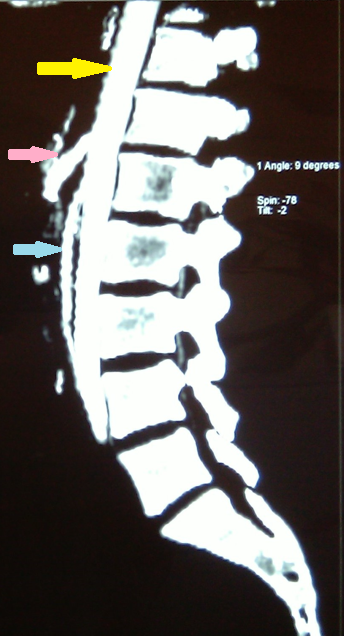

CT angiography. Yellow arrow – Aorta. Light blue arrow – Superior mesenteric artery. Pink arrow – Celiac artery (trunk of Haller). Evident significant reduction of the aortomesenteric angle to 9 degrees and the aortomesenteric distance to 4 mm. Courtesy Dr. V. Penopoulos.